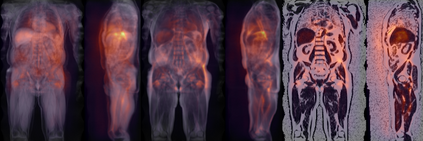

Along with rich health-related metadata, an ongoing imaging study has acquired MRI of over 40,000 male and female UK Biobank participants aged 44-82 since 2014. Phenotypes derived from these images, such as measurements of body composition, can reveal new links between genetics, cardiovascular disease, and metabolic conditions. In this retrospective study, six measurements of body composition were automatically estimated by ResNet50 neural networks for image-based regression from neck-to-knee body MRI. Despite the potential for high speed and accuracy, these networks produce no output segmentations that could indicate the reliability of individual measurements. The presented experiments therefore examine mean-variance regression and ensembling for predictive uncertainty estimation, which can quantify individual measurement errors and thereby help to identify potential outliers, anomalies, and other failure cases automatically. In 10-fold cross-validation on data of about 8,500 subjects, mean-variance regression and ensembling showed complementary benefits, reducing the mean absolute error across all predictions by 12%. Both improved the calibration of uncertainties and their ability to identify high prediction errors. With intra-class correlation coefficients (ICC) above 0.97, all targets except the liver fat content yielded relative measurement errors below 5%. Testing on another 1,000 subjects showed consistent performance, and the method was finally deployed for inference to 30,000 subjects with missing reference values. The results indicate that deep regression ensembles could ultimately provide automated, uncertainty-aware measurements of body composition for more than 120,000 UK Biobank neck-to-knee body MRI that are to be acquired within the coming years.